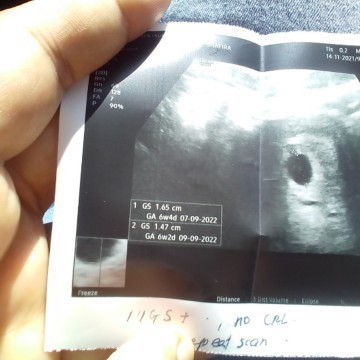

ada x ibu2 macm sy .. mmm sptutnya 9 minggu tp scan kosong + kantung size 6minggu ++ .. nak tnya masih ada peluang ke . sbb td doktor nak bg surat refer hsptal utk dnc tp sy mintak masaa lg 2 mingu ...

Baca lagiBg sy elok tunggu lg 2 minggu dan scan semula di klinik lain. Bg sy normal utk usia kandungan bila scan lari sikit dr anggaran usia kandungan dr kiraan tarikh period sbb tempoh persenyawaan apa semua kita tk tau bila secara tepat ianya berlaku. Banyak dah kes kt sini yg doktor suruh refer hospital utk dnc, tp bila scan semula tgk dh ada perkembangan dan ada bunyi jantung baby.

Baca lagisaya pun lari juga . ikutkan 7w 6hari tapi scan 6w 3days . tp doc scan nmpk kntung dan baby dlm 0.5cm kcil lg . hihi .sy kna dtg scan lg 4w lagi . doc bg ubat so kna mkn je .